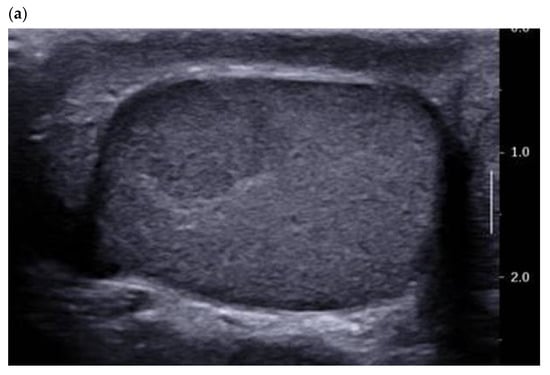

A PubMed search for articles between 2011 and 2021 using the key words Leydig cell tumour/tumor—ultrasound/sonography yielded 75 references, 28 of which were case reports. B-mode ultrasound is the most studied imaging modality in the literature, as it is the reference for examination of the scrotum. In 2015, we reported the characteristics of 38 LCT:100% were solid and homogeneous, 68.4% of which were infracentimetric (median size 7.0 mm) [10]. The most voluminous LCTs were round or lobulated and most were hypoechogenic compared with the adjacent clearly demarcated pulp (Figure 1).

Figure 1.

28-year-old patient presenting with left testicular pain (significant left varicocele during the exam). Typical LCT 12 × 9 mm on B mode us (a) and color Doppler (b) discovered on the right testis. Well-defined lobulated solid lesion moderately hypoechoic and homogeneous echo structure with normal adjacent pulp and absence of microlithiasis. The lesion is hyper vascularized with a mixed peripheral and internal pattern. (c) From left to right: Macroscopic view of the patient’s LCT after enucleation. The typical “golden brown” color of the lesion often allows the surgeon and the pathologist to confirm the diagnosis during surgery. HE × 30 Hematein–Eosin coloration showing a high cellular density with no necrosis. HE × 40 with an endothelial cell marker anti CD-31, showing a rich vascularization of the tumor. Courtesy of Pr S. Ferlicot, Department of Anatomo-pathology, Bicêtre Hospital.